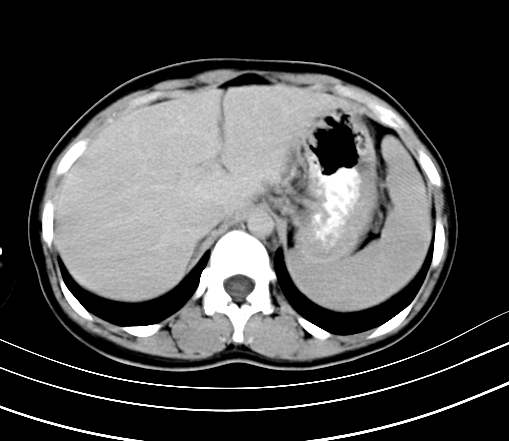

胸部

腹部平扫